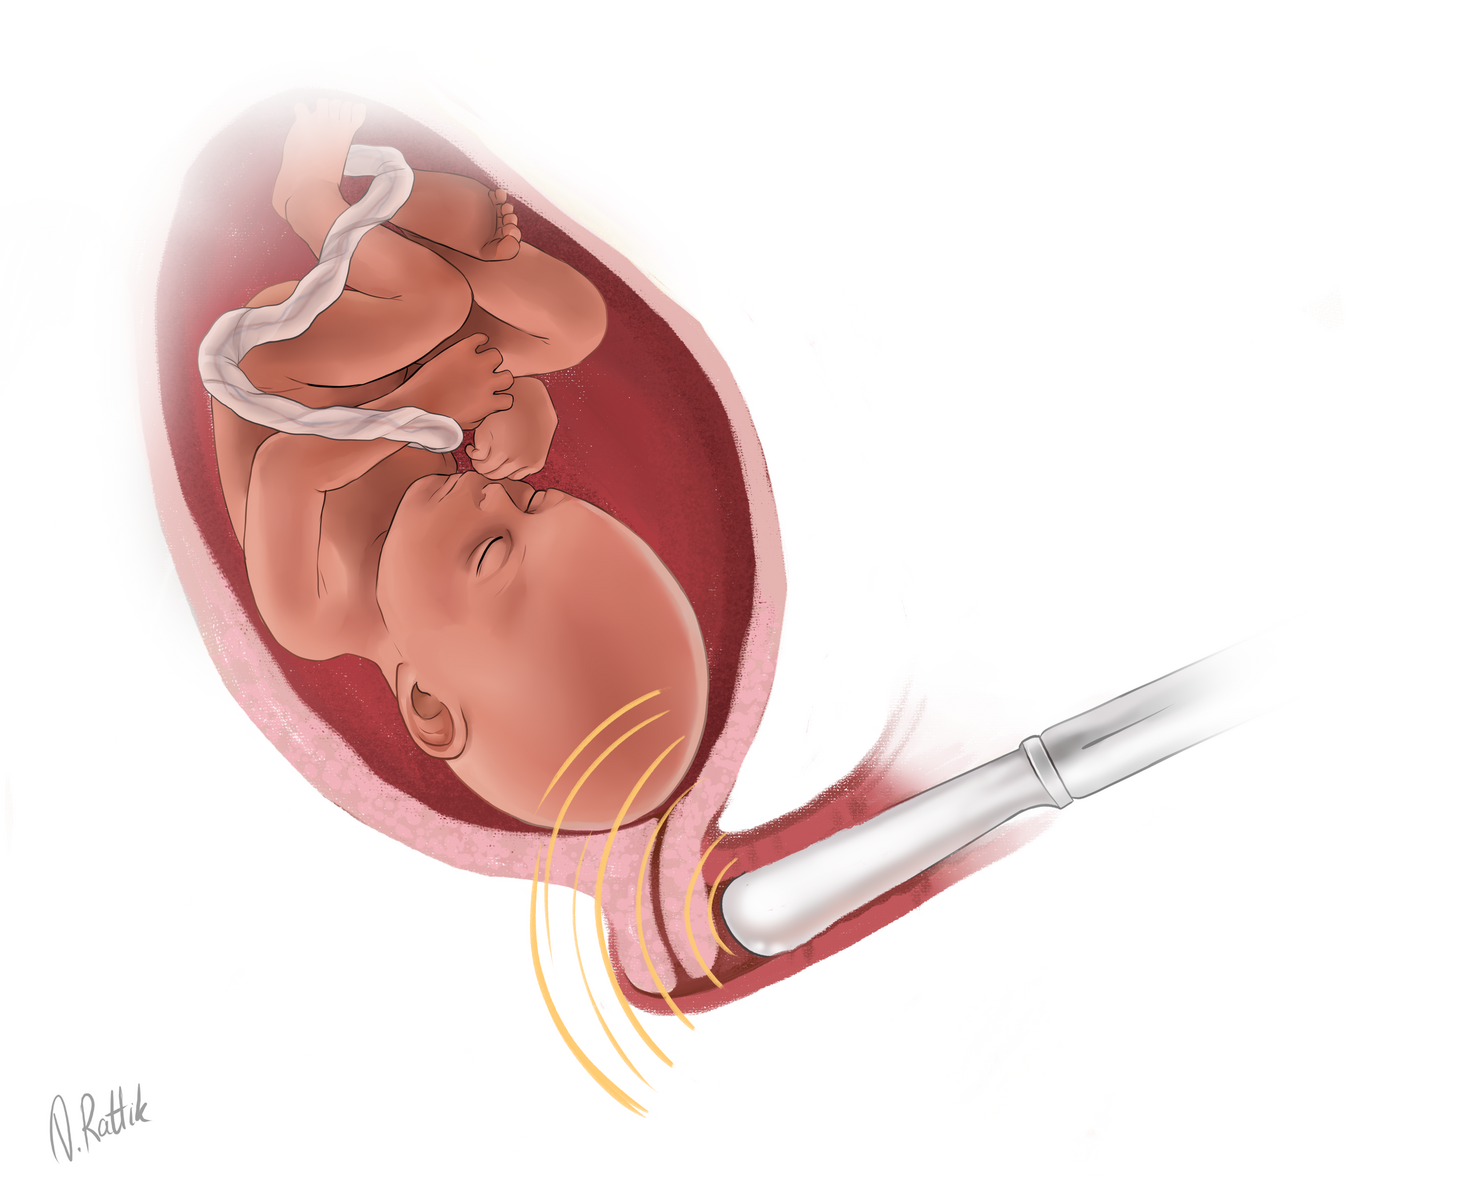

Медицинские аспекты мекония в околоплодных водах